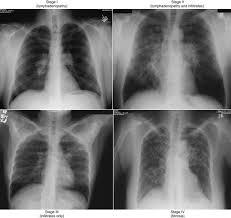

Chest X Ray For The Diagnosis Of Lung Cancer from www.verywellhealth.com Lung cancer has a low survival rate regardless of whether or not copd is also present. Smoking causes diminished overall health. Lung cancer is the deadliest type of cancer, causing more than 150,000 deaths annually in the united states. Emphysema and chronic bronchitis are two conditions that make up chronic obstructive pulmonary disease (copd). Both copd and emphysema seem to increase the risk of developing lung cancer, being this risk higher for smokers with heavier tobacco consumption. Because of that most alternative cancer treatments will not treat emphysema. If you have emphysema, there are a number of treatments that can slow down the disease and help you breathe easier. Most lung cancers do not cause any symptoms until they have spread, but some people with early lung cancer do have symptoms.

Study Finds Evidence That The Presence Of Emphysema On A Ct Scan Increases Lung Cancer Risk from lungdiseasenews.com Emphysema involves gradual damage of lung tissue, specifically thinning and destruction of the alveoli or air sacs. Lung cancer is a disease of uncontrolled cell growth in lung tissues. Both copd and emphysema seem to increase the risk of developing lung cancer, being this risk higher for smokers with heavier tobacco consumption. Emphysema is not lung cancer. The main symptom of emphysema is shortness of breath, which usually begins gradually. This article will explain what lung cancer is, how to recognize. Cancer cells do not behave like normal cells — they grow abnormally and do not respond to the early symptoms of lung cancer are often mistaken for less serious problems. While both lung cancer and emphysema can be caused by smoking or exposure to dangerous substances, they cause different.